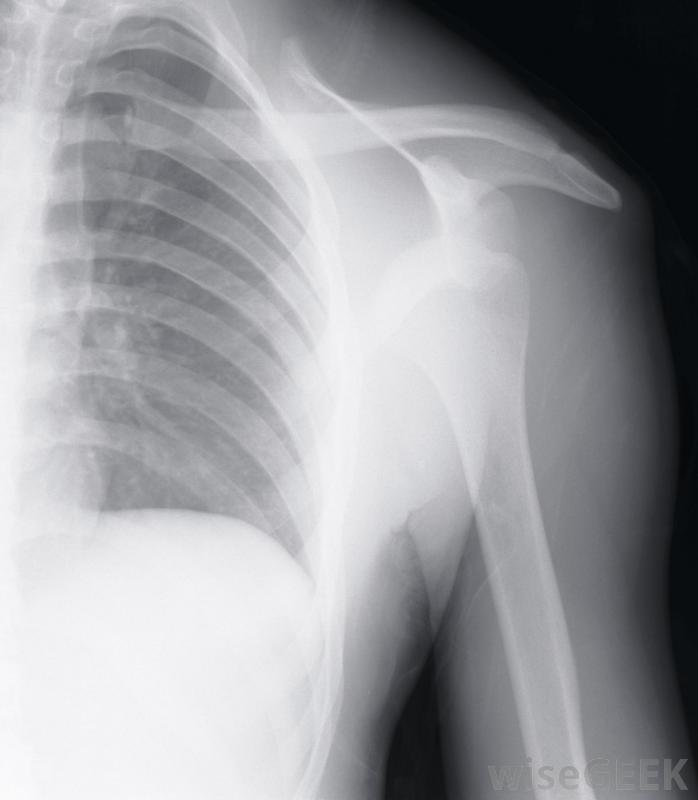

肩关节劳损的根本原因可以从X光片中发现关节炎和缺血性坏死等退行性疾病也可能是肩部劳损和疼痛的根源,关节炎会磨损软骨,甚至会影响肩关节骨的强度。炎症开始,使肩膀很难正常移动通常情况下,需要药物来控制炎症,并帮助患者获得至少一些缓解疼痛的效果。

一个包括肩部许多肌肉的解剖图随着缺血性坏死,肩部骨骼的血液供应中断,这导致骨骼慢慢地饥饿和萎缩。随着骨骼的死亡,如果没有剧烈的疼痛,肩关节的正确旋转是不可能的。通常,手术是唯一的解决办法,虽然在疾病的早期阶段使用药物是有帮助的,但是诊断肩关节劳损的潜在原因至少需要进行一次身体检查。通常,主治医生也会要求检查X光或磁共振成像,也被称为核磁共振成像。这有助于确定疼痛的原因是由于过度劳累,还是有一个正在发展中的健康问题必须解决,以减轻由劳累引起的不适肩关节劳损的治疗过程中可能有几个因素。使用消炎药是相当普遍的。根据劳损的原因,在一天中对肩部进行热敷和冷敷可能有助于消肿和减轻一些疼痛物理治疗也可能是必要的,以帮助恢复一定的运动范围和帮助促进受损组织的愈合。在大多数情况下,手术通常被认为是最后的手段,出现缺血性坏死是一个明显的例外